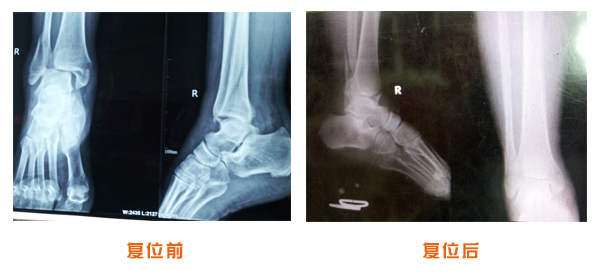

復(fù)位前后對(duì)比

踝關(guān)節(jié)脫位骨折治療前后對(duì)比